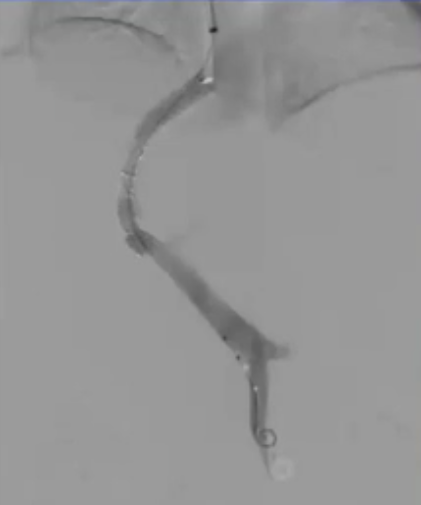

急性门静脉血栓(续) 对于那些成功实施经颈静脉经肝到达门静脉内急性血栓内,并进行了溶栓和抗凝治疗的患者,是否应该进行经颈静脉肝内门体分流术(TIPS)呢(放支架)? 这一问题存在争议。 。一个过于激进的TIPS手术,导致门静脉分支没有血流,从而发展成肝硬化 妥协的操作是设置一个“小TIPS”,即放置一个直径较细(直径5毫米左右)的TIPS裸支架,溶栓导管经支架通过,进行抗凝和溶栓治疗后,同时保留 TJ 对 SMV/PV 的访问权限,以防再次发生血栓情况。 一例术后急性门静脉血栓病例,最终影像显示门静脉根部血流情况良好,这还不够理想,担心会再次发生血栓,且门静脉压(PSG)超过 12 毫米汞柱,因此增加了经导管动脉溶栓术(TIPS)的治疗方案。

通过经皮经脾路径具有显著优势,能够使用 4Fr 细导管和导丝进行逆向再通操作,以 10 毫米的圈套器作为经颈静脉穿刺目标,通过Avitene 完成经颈静脉门静脉穿刺。